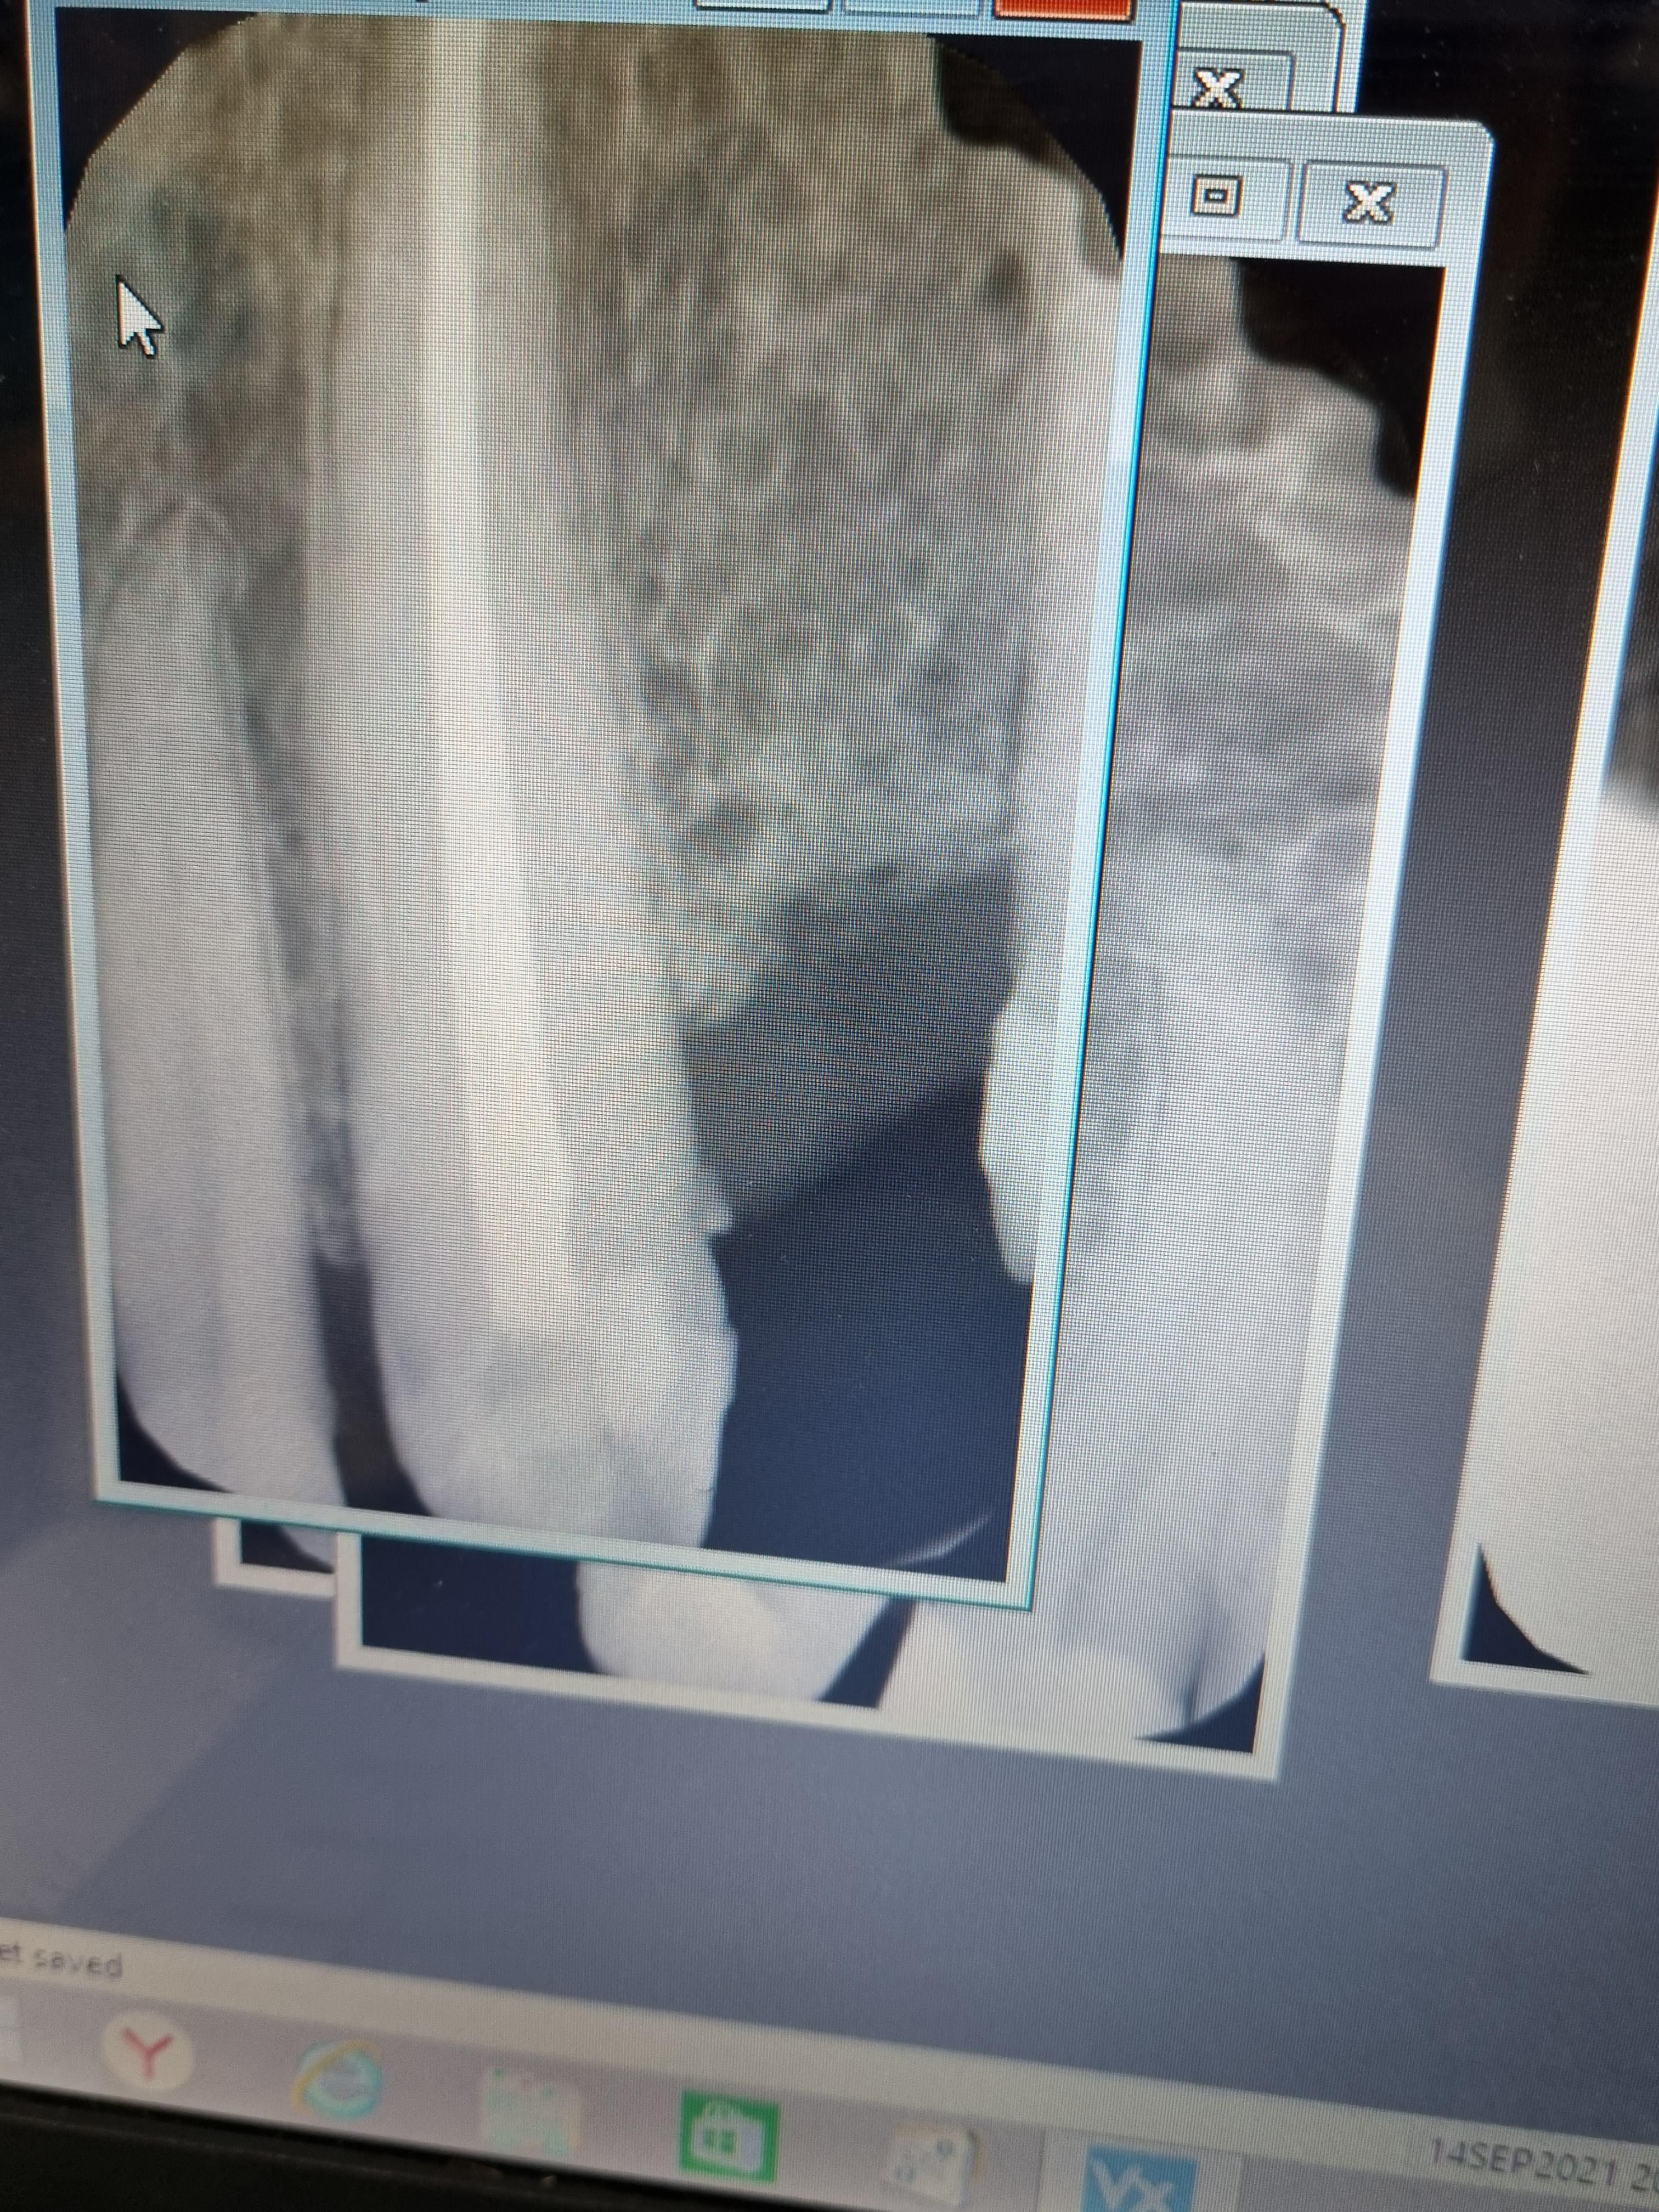

Пациент направлен врачом стоматологом-ортопедом для перелечивания 2.3 зуба из-за хронического апикального периодонтита.

Хронический апикальный периодонтит заключается в воспалении тканей апикального периодонта, чаще всего бессимптомном. Проявляется рентгенологическими изменениями на верхушках корней зуба.

В ходе лечения врач провёл следующие манипуляции:

- распломбировка;

- эндодонтическая обработка корневого канала с применением системы коффердам;

- постоянная пломбировка первого корневого канала;

- восстановление коронковой части зуба с помощью временного пломбировочного материала;

- протезирование.